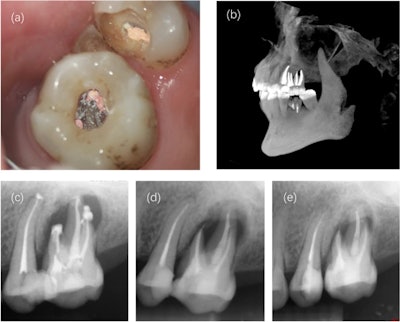

After treatment was completed successfully, the woman was scheduled for follow-up visits. At the one-year follow-up visit, the tooth remained free of symptoms, and imaging showed the tooth had a healing apical area.

Immediate postoperative and follow-up imaging. (a) The filled root canal under an operating microscope. (b) A 3D reconstruction of filled tooth #26. (c) A periapical radiograph taken after treatment. (d) A radiograph taken at the six-month follow-up. (e) A radiograph taken one year after the root canal.